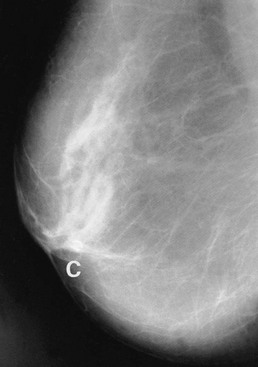

A typical carcinoma appears as a spiculated mass lesion (dense centre with radiating lines) which may have malignant-type fine linear or granular microcalcification (Fig. 45.5). Fine granular microcalcification within a spiculate lesion is virtually pathognomonic of cancer. Tumours as small as 2–3 mm are sometimes detectable radiologically, long before they become palpable.